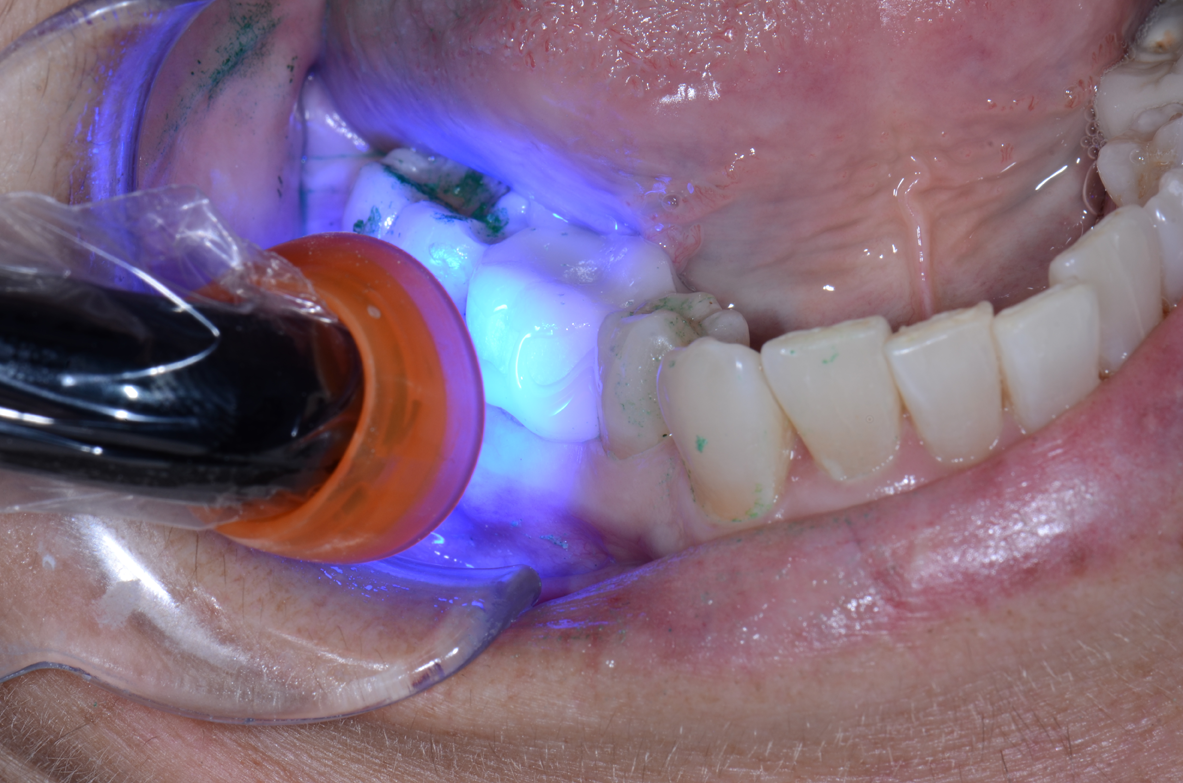

3. Apply pressure and use an explorer to determine whether or not the provisional is fully seated. Cure the material with an LED curing light for no more than one to two seconds from the lingual and repeat on the buccal. The material will now peel off easily and excess can be removed with an explorer or scaler (Figs. 12-15).

Fig. 13 Fig. 14 Fig. 15

4. Floss the contacts to remove excess that is wedged interproximally. Using your light-curing unit, cure for 20 seconds from the buccal and then again on the lingual. This will increase the translucency and the set of the material. The chemical cure time of the cement is six to seven minutes intraorally. A final light curing facilitates easy and efficient cleaning of the excess while increasing the initial cure. The set of the material is sufficient to rinse the patient, sit them up to deliver post-op instructions and ultimately release them.